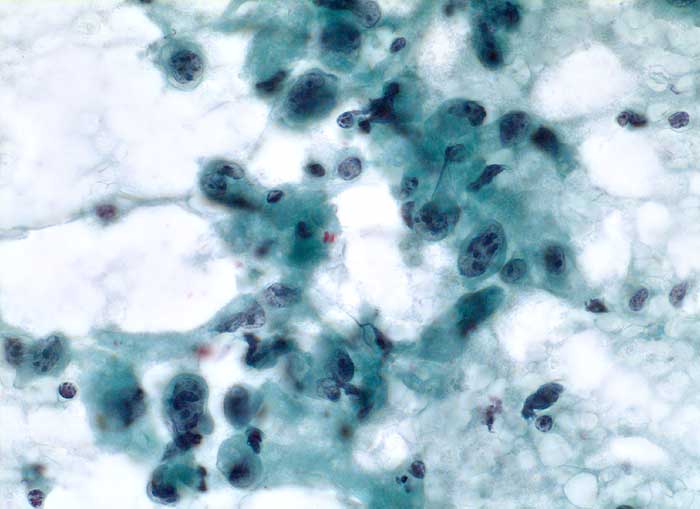

Anaplastisches Schilddrüsenkarzinom

Feinnadelpunktion Schilddrüse: Der Ausstrich enthält atypische Zellen, welche wesentlich grösser sind als regelrechte Schilddrüsenepithelien. Die Tumorzellen sind ein oder mehrkernig. Die Kerne sind stark polymorph, grob strukturiert mit meist mehreren plumpen Nukleolen. Das Zytoplasma ist unterschiedlich breit.

Strumaknoten links mit Einengung der Trachea

Zytologie

400